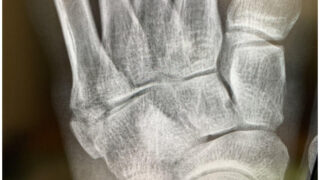

明日は金沢マラソンです。本来であれば3時間45分のペースランナーとして出走予定でしたが、ブログをご覧になって頂いている方はご存知のように第5中足骨骨折により出走できません。自分の本来のレースではありませんが、無性に悔しい。それは地元のマラソ...

骨折して一週間今日は治療の日

今更なんですが。昨日届いたハガキ。20キロ。1キロ辺り4分8秒。河川敷というフラットなコースではありますが、前半突っ込み過ぎなのを抑えた感じで最後上げられたのですから結果的には良いレースだったのかと思います。本当のレースではないけど。そのま...

久しぶりの飲み会で少しは経済回りだしたかも。

昨晩は蔓延防止措置あけで久しぶりに外飲みでした。ラン仲間と。そして二次会まで。怪我したのを励ましてくれるサプライズプレートも有難うございました。正直言ってむちゃくちゃ悔しいけど。治します。そして早く復帰します。必ず。多分ランナーでここを骨折...

金沢マラソン前に悲惨なできごとが。